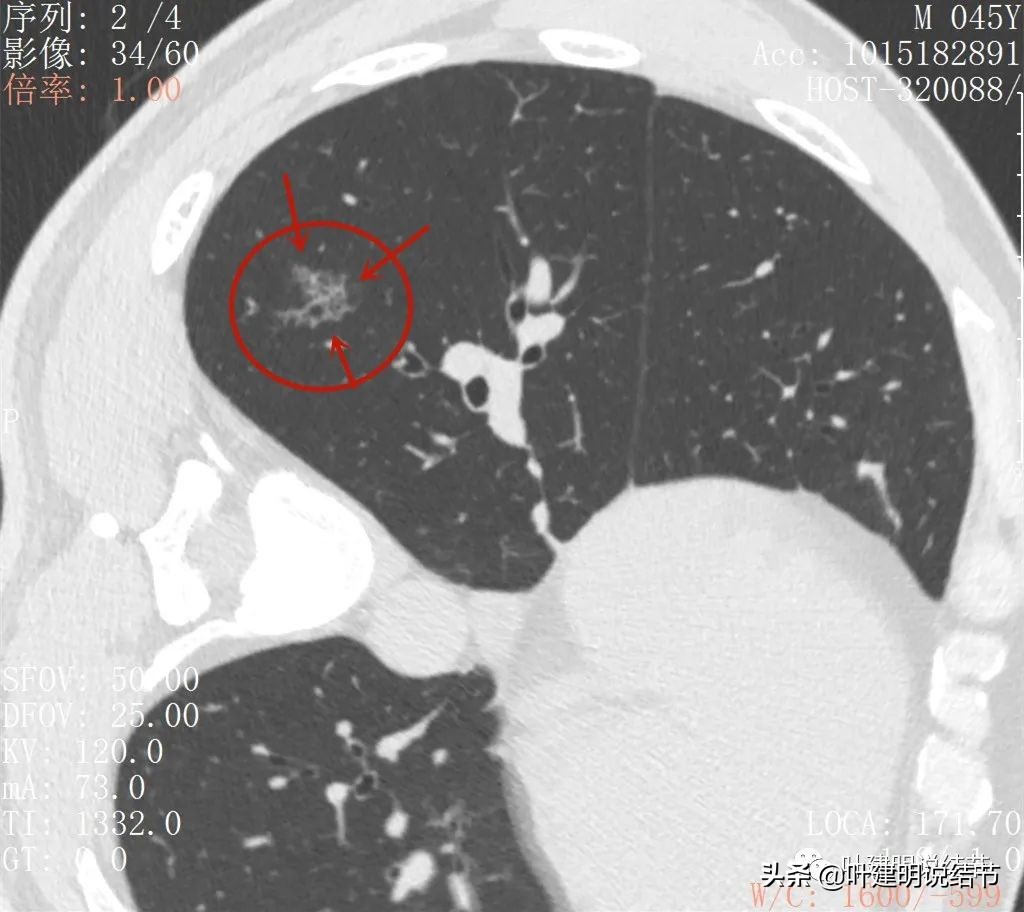

2022年2月平扫:

右下叶淡而散在的磨玻璃影

整体轮廓有点清楚,似见血管走行于病灶处

密度略不均